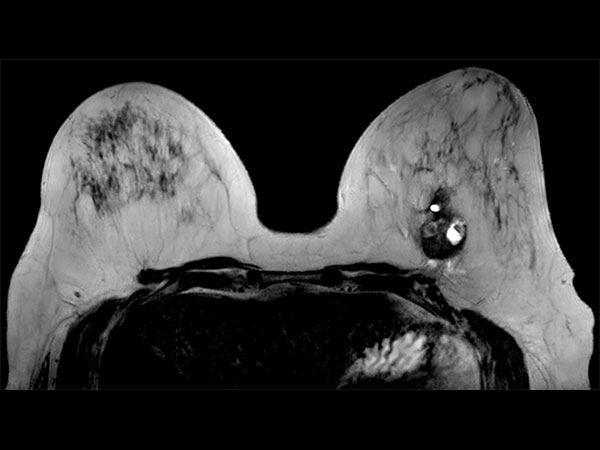

57 year old female with a new diagnosis of Ca. Sample obtained by US biopsy: Invasive Ductal Ca, grade 3. MR requested to aid in determining treatment.

Axial T2w 3D TSE (VISTA)